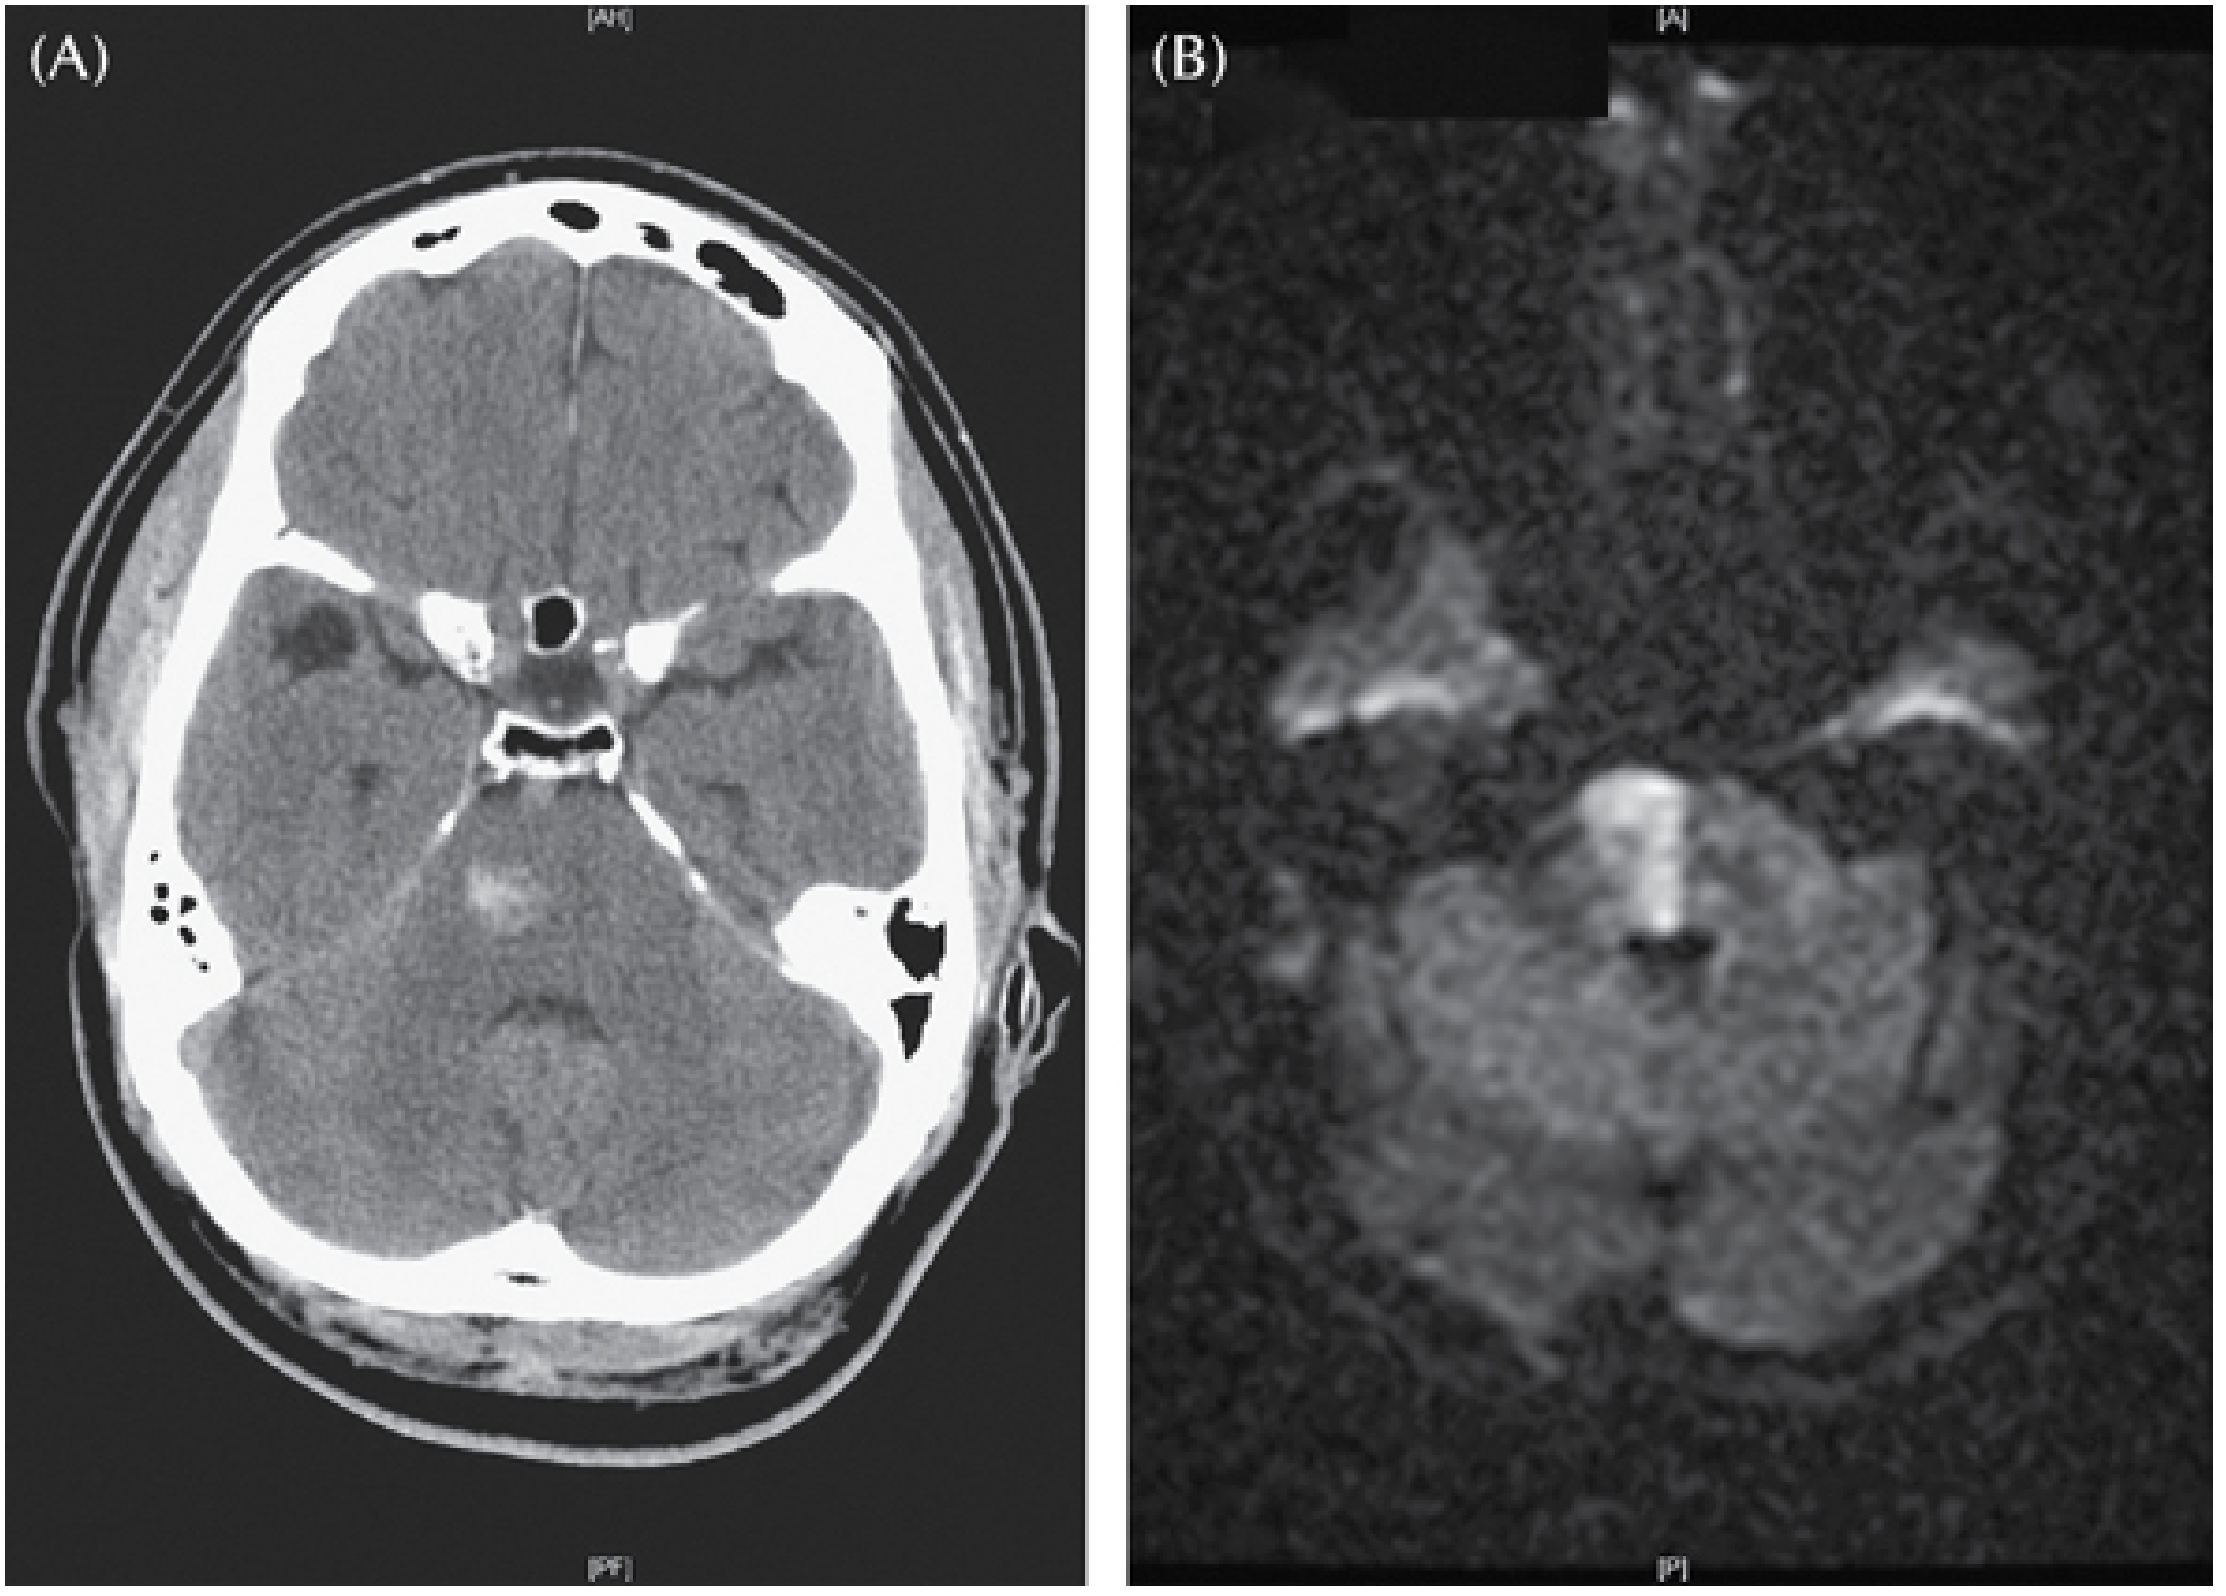

Imaging: Non-contrast CT is the first-line investigation — the haematoma appears as a hyperdense lesion in the pons. MRI (T2*/SWI) is more sensitive for small tegmental bleeds and cavernous malformations.

Imaging

CT and DWI MRI of pontine stroke: (A) CT showing right pontine base and tegmentum haemorrhage; (B) DWI showing medial pontine infarct

(A) Non-contrast CT showing a small haemorrhage into the right pontine base and tegmentum in a hypertensive patient presenting with left hemiparesis and dysarthria. (B) DWI MRI of a medial pontine infarct for comparison. — Plum and Posner's, Fig. 4.8